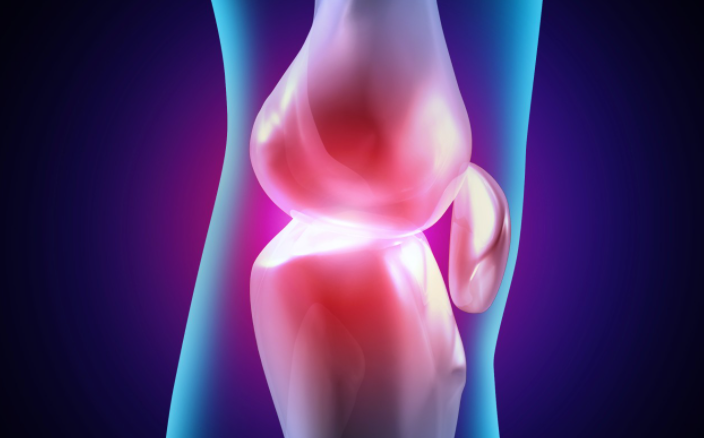

연골은 움직일 때 관절과뼈를 보호하는 쿠션입니다. 그러나 나이가 드신 분들이나 골관절염 환자의 경우에는 연골이 시간이 지남에 따라 마모되어 통증과 불편함을 유발할 수 있습니다.

골관절염은 노년기와 관련이 없는 경우가 많지만 연골은 모든 사람이 다양한 속도로 퇴화됩니다. 따라서 연령이나 상태에 관계없이 연골을 보호, 유지, 보충 및 복구할 수 있는 영양가 있는 음식을 섭취하는 것은 권장합니다.

연골 보호

골관절염은 전 세계 수백만 명의 사람들에게 영향을 미치는 질환입니다. 그러나 그것에 대한 보호하고 연골을 회복하는 방법과 음식이 있습니다.

연골 마모는 자연적으로 발생하며 완전히 멈출 수 없다는 사실을 알아야 합니다. 그러나 건강한 생활 방식을 유지하면 연골 회복을 촉진할 가능성이 높아집니다.